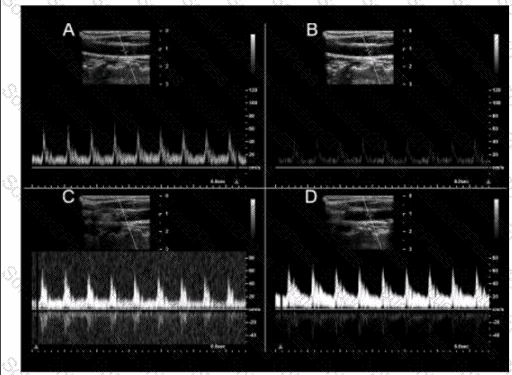

Which pulsed-wave Doppler adjustment would be appropriate to correct the aliasing seen in this image?

A.

Increase the spectral Doppler gain.

B.

Decrease the spectral Doppler gain.

C.

Increase the Doppler pulse repetition frequency.

D.

Decrease the Doppler pulse repetition frequency.

Which image demonstrates appropriate spectral Doppler gain?

Option A

Option B

Option C

Option D